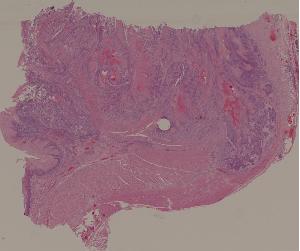

27. Squamous cell carcinoma of the esophagus